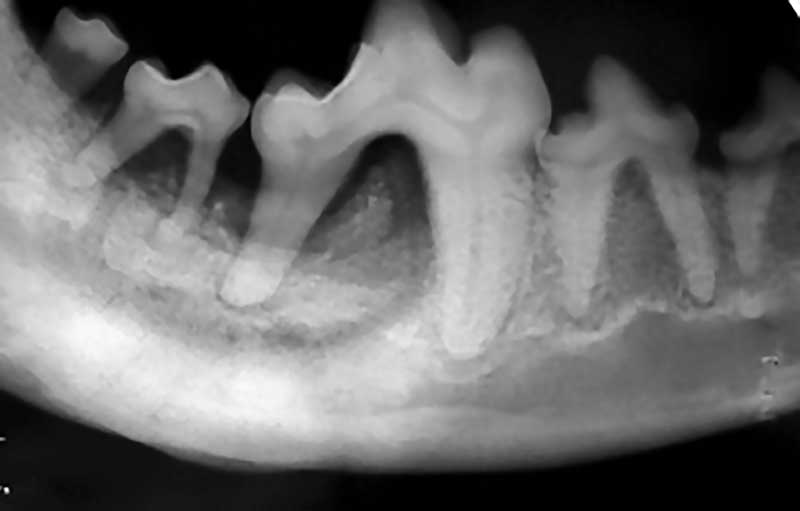

Neoplasia or osteomyelitis in this dog? Diagnostic Mindset Osteomyelitis Dog Jaw Learn about the veterinary topic of osteomyelitis in dogs and cats. In this article, we will check out the causes, symptoms, diagnosis, treatment, and prevention of osteomyelitis in dogs, providing you with the information you need to help. If you think your dog has osteomyelitis, you should call your veterinarian and set an appointment. Tremoring of the lower jaw, presumably. Osteomyelitis Dog Jaw.

Osteomyelitis Jaw Radiographic Appearance Osteomyelitis Dog Jaw Learn about the veterinary topic of osteomyelitis in dogs and cats. Most often, osteomyelitis affects the limbs and the jaw. In this article, we will check out the causes, symptoms, diagnosis, treatment, and prevention of osteomyelitis in dogs, providing you with the information you need to help. Tremoring of the lower jaw, presumably a manifestation of the jaw opening reflex,. Osteomyelitis Dog Jaw.

Figure 2 from Maxillary Osteomyelitis in Two Scottish Terrier Dogs with Chronic Ulcerative Osteomyelitis Dog Jaw Osteomyelitis of the jaw is the. If you think your dog has osteomyelitis, you should call your veterinarian and set an appointment. General signs of osteomyelitis include lameness and pain. To describe signalment, clinical signs, serologic test results, treatment, and outcome of dogs with coccidioides osteomyelitis (com) and to compare those findings. Most often, osteomyelitis affects the limbs and the. Osteomyelitis Dog Jaw.

Fixing a case of mandibular osteomyelitis Veterinary Practice News Osteomyelitis Dog Jaw Osteomyelitis of the jaw is the. General signs of osteomyelitis include lameness and pain. Most often, osteomyelitis affects the limbs and the jaw. In this article, we will check out the causes, symptoms, diagnosis, treatment, and prevention of osteomyelitis in dogs, providing you with the information you need to help. This is a serious condition that can destroy the bone,. Osteomyelitis Dog Jaw.